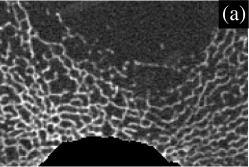

For each proximal tibia, an axial QCT slice was acquired 17 mm below the tibial plateau with a Stratec XCT-2000 pQCT scanner (Stratec GmbH, Pforzheim, Germany), with an in-plane pixel size of 200 m 200 m and a slice thickness of 1 mm. In some cases, the scans were performed after the biopsies were taken. Therefore, the holes left from the bone biopsy appear in some of the pQCT images. A standardised image pre-processing procedure was applied to exclude the cortical shell from the analysis. Saparin et al. (1998); Saparin, Gowin, and Felsenberg (2002); Saparin et al. (2006) One of the resulting images is shown in Fig. 1.

III.6 Illustration

To illustrate the analytical method, we now present the results in visual form for an enlarged region near the bottom (posterior) of the slice in Fig. 1. The enlarged region of the original image is shown in Fig. 3(a). Parts (b) to (e) of Fig. 3 show directional strand strengths, and part (f) shows the final node strength plot. Each directional strand strength plot shows the sum of two strand strengths at every pixel, in opposite directions: east/west; north/south; northwest/southeast; and northeast/southwest. In each of the directional strand strength plots, the strands in the given direction are shown with the highest intensity, but most of the trabeculae are still visible, even if faintly. In contrast, in the node strength plot (part (f)), most of the trabeculae are invisible. This is because of the subtraction of the minimum strength constant. In this example, there are almost no nodes in the right half of the image. This correctly describes the micro-architecture of the original image in that region, which contains many trabeculae but few that cross each other to make a lattice-like micro-architecture. The left half of the image contains many nodes. Notice that, in the node strength plot, the nodes seem to be thicker than in the original image. This is because the trabeculae in the original image are actually slightly thicker than they appear, the outer pixels being dimmer (i.e. lower CT values) and thus not easily registered by the eye. Since the outer pixels near the apparent nodes in the original image are almost as well-connected as pixels in the centres of the nodes, they have large node strengths, and are very visible in the node strength plot.